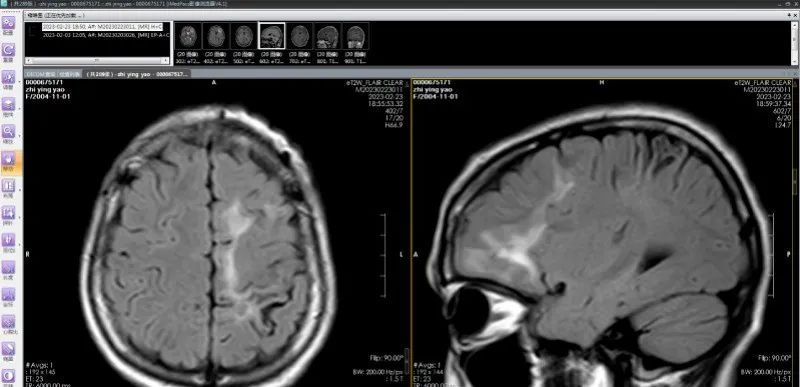

经过系列相关检查,发现彤彤左侧额叶存在多发病变,且两次发作症状不尽相同,怀疑是寄生虫感染。进一步检查结果提示:裂头蚴IgG抗体阳性;视频脑电图显示:左侧额顶叶多发放电。

多发脑软化灶实为虫体在颅内爬行产生的损伤,患者癫痫发作的根源在于寄生虫对大脑的炎性刺激,造成大脑异常放电。

脑软化灶实为虫体在颅内的爬行轨迹;(左)从下往上移动,(右)从后往前移动